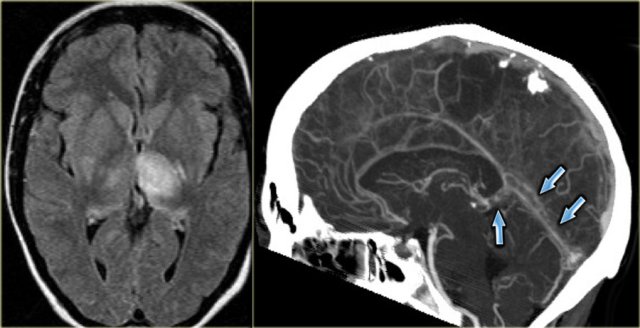

On the far left a FLAIR image demonstrating high signal in the left thalamus.

When you look closely and you may have to enlarge the image to appreciate this, there is also high signal in the basal ganglia on the right.

These bilateral findings should raise the suspicion of deep cerebral venous thrombosis.

A sagittal CT reconstruction demonstrates a filling defect in the straight sinus and the vein of Galen (arrows).